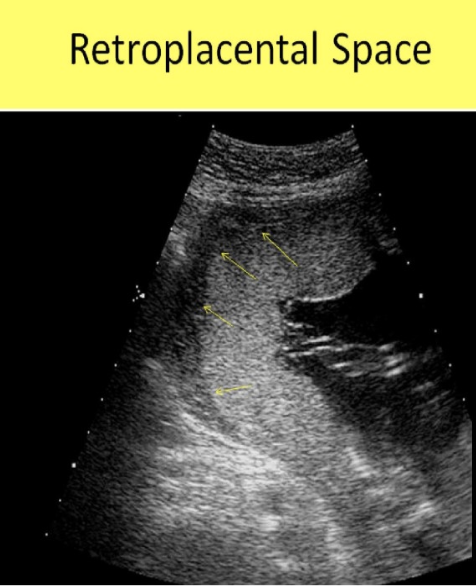

which abn can be r/o by the presence of a normal retroplacental space

a) placenta previa + circumvallate placenta

b) placenta accreta + placental abruption

c) fluid in posterior CDS

d) fluid in anterior CDS